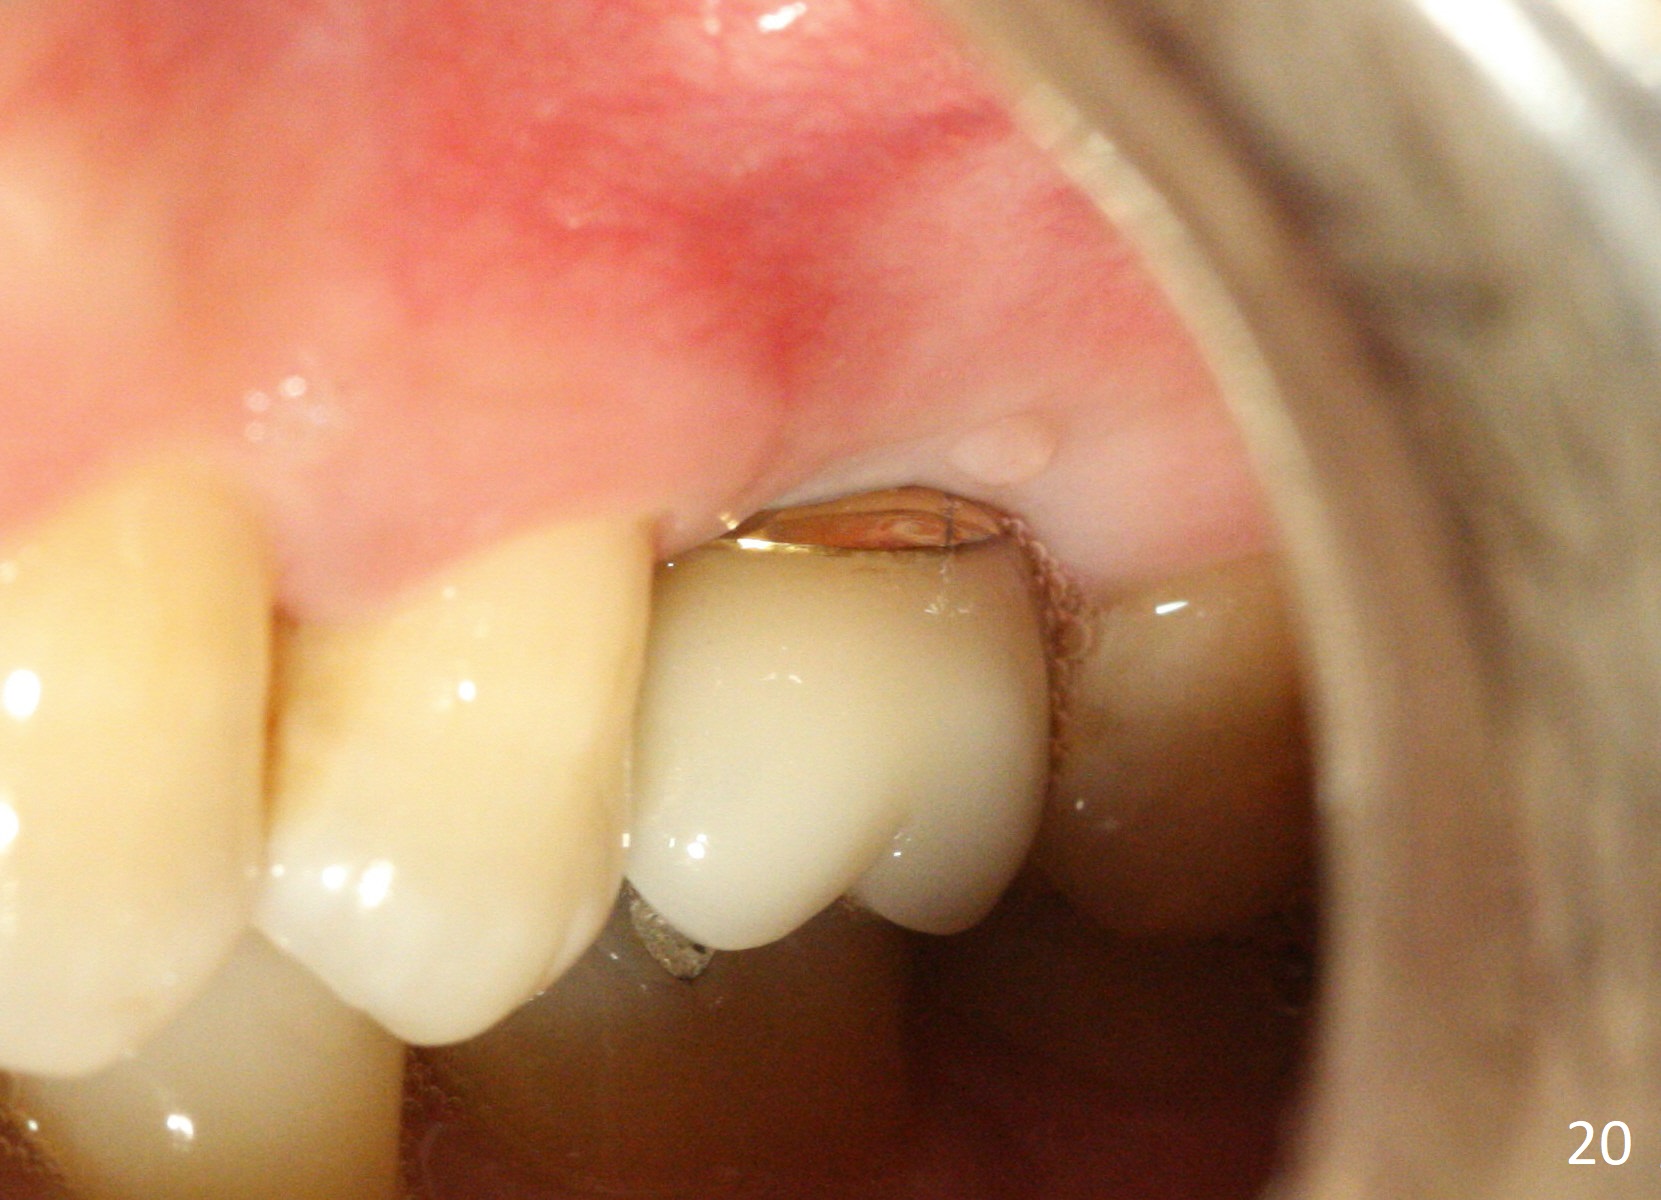

A 45-year-old man has lost the tooth #14 for a while (Fig.1); bone height is 5.4 mm. An extra wide and short implant is planned. Torus palatinus is large, suggesting that bone density should be high. A 6 mm tissue punch is chosen, but it is placed more palatal. If it were placed in the middle of the ridge, there would be no buccal keratinized gingiva (incision may avoid this issue). Additionally, the buccal portion of punch is made incomplete so that there is pedicle on the buccal side when the flap is raised (Fig.4,8: F). It is expected that the excess portion of keratinized tissue will form thick gingiva buccally. Osteotomy proves that bone is dense (Fig.2 (4.5x11 mm tap). Typical sinus lift is finished with placement of 6.4x6 mm (extra wide) bone-level implant (Fig.3, >55 Ncm). Following further torque, Fig.4 shows that the implant (I) is sub-gingival (<). Bitewings are taken to confirm that the implant plateau is at the crestal level (Fig.5,6 ^). PA shows sinus lift (Fig.7 *). The lingual aspect of the implant and healing abutment (H) is further bone grafted and covered by collagen dressing (Fig.8 *). The wound is protected with perio dressing. When the latter dislodges 7 days postop, the collagen dressing and bone graft are lost as well (Fig.10), while the buccal flap remains vital (Fig.9). The lingual exposed plateau should be able to heal normal. The collagen dressing should have been fixed in place by suture or as simple as a dental floss. There is mild nasal hemorrhage 1-2 days postop, possibly related to sinus membrane perforation and inability of Collagen Dressing to cover the perforation and contain the bone graft. When the patient returns for #9 implant placement in 3 weeks postop, the buccal flap reduces in size (Fig.11 *), while the palatal wound has healed with minimal exposure of the implant (Fig.12). Sinus graft remains in place 3 months postop (Fig.13); the buccal flap appears to have incorporated into a part of the gingiva (Fig.14). The bone density of the sinus lift appears to increase 10 days later when an abutment is placed (Fig.15 *). Although oral hygiene is pristine, there is apparent crestal bone resorption 12 months (Fig.16) and 20 months (Fig.17) post cementation, probably due to unfavorable crown/implant ratio and bruxism as well as pre-implantation bone loss (Fig.18,19). In contrast, an immediate implant in the same patient avoids pre- or post-implantation bone loss. In fact both the soft (Fig.20) and hard (Fig.21) tissues remain healthy 2 years 8 months post cementation. The sinus lift remains 3 years 8 months post cementation (Fig.22), while the crestal bone loss persists. The patients keeps complains of food impaction distal associated with bad smell 4 years 1 month post cementation. In fact the distal proximal contact is within normal limit. The bad smell is probably due to crestal bone loss (Fig.23 (pan), 24 (CT) *) and periimplantitis. Bone graft, PRF and Cytoplast membrane will be needed and fixed in place with long healing screw. When the patient returns for crown redo, he also reveals floss related gingival hemorrhage. There is pain associated with palatal sulcus probing with light gingiva erythema. Review of CT coronal section shows possible palatal (Fig.25 P) bone loss (*).